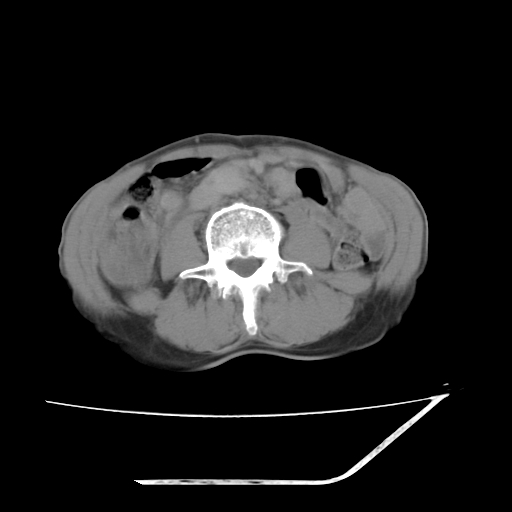

增强

考虑右肾盂癌,肾动脉受侵,右肾功能减退,右肾盂输尿管积水,管壁增厚,考虑种植转移,应该把下面扫完的

支持右侧肾盂癌伴肾静脉瘤栓形成可能性大,右肾结石.肝右叶后段低密度影,不除外转移.

右肾盂旁ca并肾静脉瘤栓形成/肾功能降低。

右肾结石。

右肾盂移行细胞癌并右输尿管中段转移.肾积水.

1.右侧肾盂癌伴肾盂积水。

2.肾脏功能减退,原因有:(1)肾动脉受侵。(2)肾静脉受侵(3)肾积水,等。本例,肾动脉显影较好,但受压明显;肾静脉无明显显示,受压或静脉癌栓,下腔静脉腔内未见明显充盈缺损。

3.右侧上段输尿管扩张,原因:(1)积水所致;(2)种植。